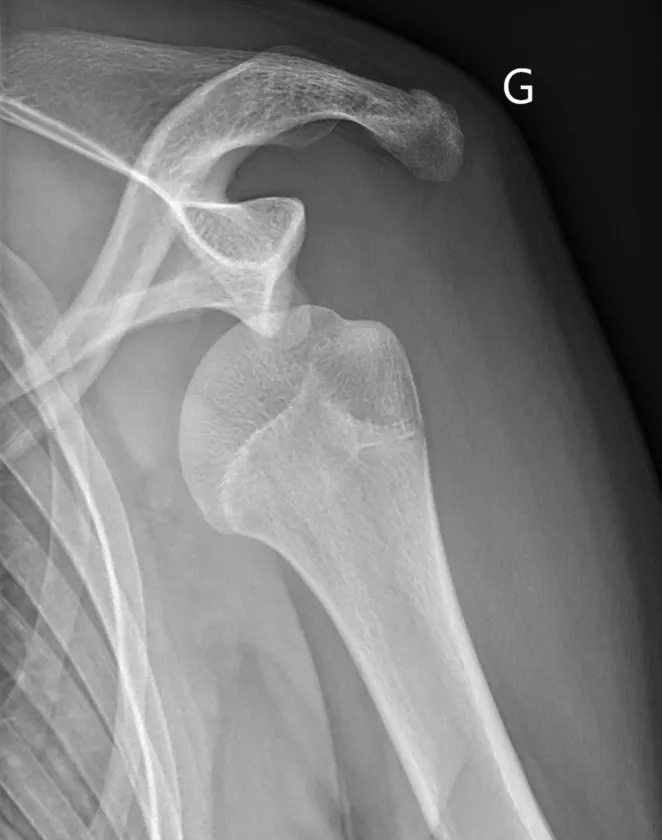

Les lésions osseuses:

Lors d'un épisode de luxation, la tête humérale venant heurter violemment la partie antéro-inférieure de la Glène, elle peut provoquer une fracture du rebord osseux de celle-ci. Lorsque la tête humérale vient s'incarcérer en regard de la glène, Elle peut également s'écraser et se déformer de façon irréversible à la manière d'une balle de ping-pong que l'on écraserait avec le doigt.

Lorsque les déformation osseuse sont importantes les techniques arthroscopiques ne suffisent pas à stabiliser l'épaule. La technique la plus appropriée est alors la réalisation d'une butée coracoïdienne. L'association d'une technique arthroscopique de réparation du bourrelet , d'une rétention capsulo-ligamentaire et un comblement de l'encoche de Hill-sachs peut être une alternative dans certains cas.